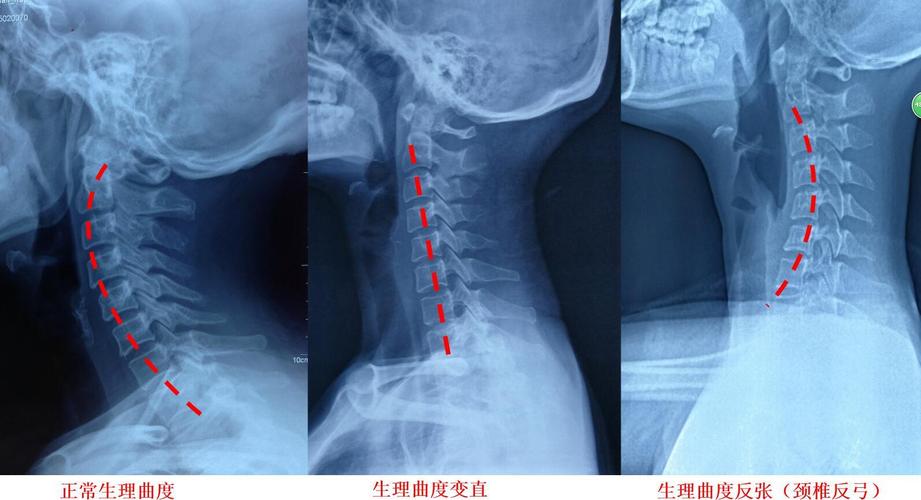

颈椎侧位的三个形态,你的是正常,是曲度变直还是反张,如果你有头疼

图03 颈椎生理曲度改变.jpg